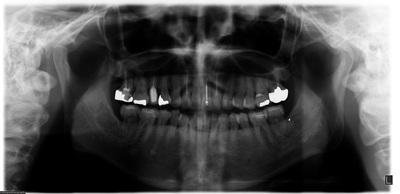

術前の状態

術前パノラマ

奥歯の違和感から見つかった"歯の亀裂"

52歳の女性の患者様です。長年にわたり定期的にメインテナンスを続けておられ、歯ぎしりの自覚があり、ナイトガードを早い段階から使用されていました。右上の奥で噛むと違和感があるとのことで来院され、前から5本目と7本目の歯の根に亀裂が見つかりました。どちらも過去に治療を重ねてきた歯でしたが、内部まで亀裂が進行しており、残念ながら保存は難しい状態でした。

奥の7本目の歯は骨の高さが足りず、上あごの空洞(上顎洞)に非常に近い位置にありました。一方で、その手前の5本目の歯は骨の厚みは十分でしたが、噛む力が強く、歯ぎしりの影響を受けやすい位置でした。同じ上あごの奥歯でも条件がまったく異なっていたため、それぞれに適したインプラントを選択しました。